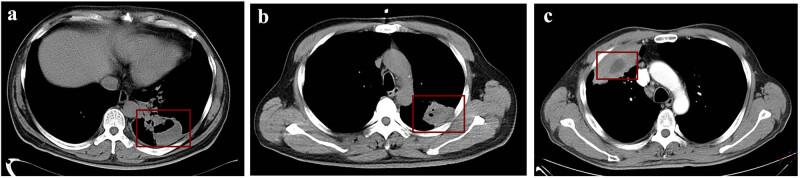

A lung abscess is a necrotizing infection caused by microbiomes that lead to the loss of healthy lung tissue. The routine culture is a waste of time and yields false-negative results, and clinicians could only choose empiric therapy or use broad-spectrum antibiotics, which could significantly contribute to the problem of resistance or aggravate the condition. We report three patients with a routine-culture-negative lung abscess. The presenting symptoms included fever, cough, dyspnea, and chest pain, and a computed tomography scan revealed a lesion in the lungs. The bronchoalveolar lavage fluid and pleural fluid were tested for pathogens using metagenome next-generation sequencing (mNGS), and the results revealed and spp. (, ) as the most represented microbial pathogens. Our data demonstrated that mNGS could be a promising alternative diagnostic tool for pathogen detection, and the pathogen lists indicate that it will be important to focus on the genus rather than the dominant spp. in terms of co-infection of pathogen determined by shotgun mNGS.

肺脓肿是由微生物群落引起的坏死性感染,可导致健康肺组织丧失。常规培养浪费时间且会产生假阴性结果,临床医生只能选择经验性治疗或使用广谱抗生素,这可能会显著加剧耐药问题或使病情恶化。我们报告了3例常规培养阴性的肺脓肿患者。主要症状包括发热、咳嗽、呼吸困难和胸痛,计算机断层扫描显示肺部有病变。使用宏基因组下一代测序(mNGS)检测支气管肺泡灌洗液和胸腔积液中的病原体,结果显示 和 菌属( , )是最主要的微生物病原体。我们的数据表明,mNGS可能是一种很有前景的病原体检测替代诊断工具,病原体清单表明,在通过鸟枪法mNGS确定病原体合并感染方面,关注 菌属而非占主导地位的 菌属将很重要。